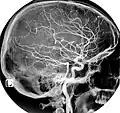

Magnetic Resonance Angiography- Normal carotidal arteriography